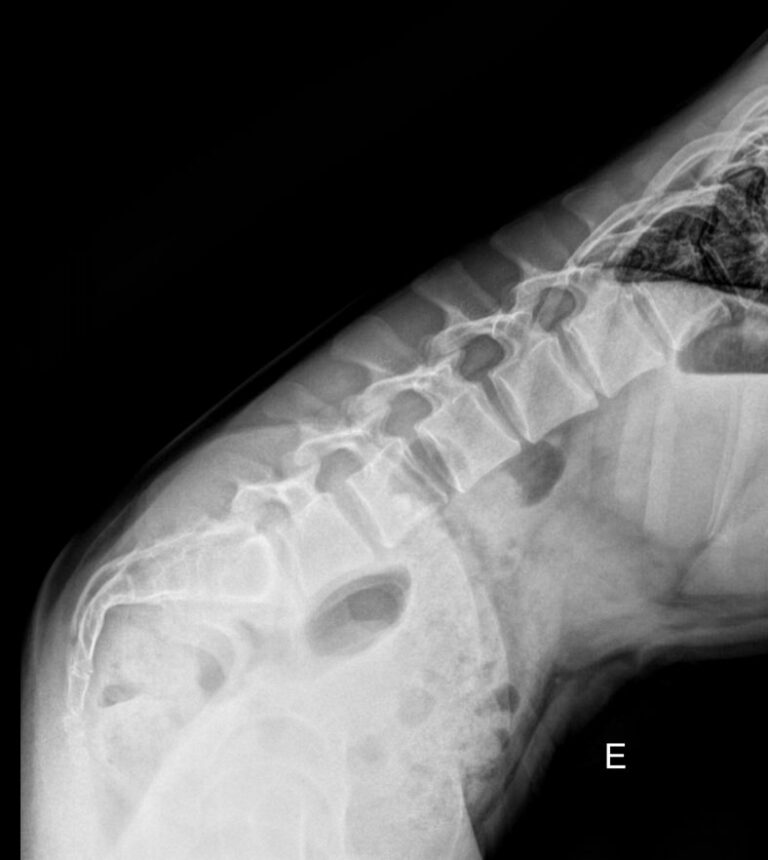

В исследование входит 3 снимка, показывающих состояние поясничного отдела в разных положениях. Однако бояться чрезмерного облучения не стоит: цифровые модели рентгеновского оборудования последнего поколения излучают минимально необходимую для четкого снимка дозу. После данного исследования количество облучения, полученного организмом, будет составлять едва ли десятую часть от допустимой годовой дозы.

На первом снимке будет видно, сохранен ли естественный поясничный лордоз или есть его изменения. На тестовых снимках будут видны:

• Изменение высоты межпозвонковых дисков при отсутствии патологий;

• Неизменность межпозвонковых пространств при наличии функционального блока;

• Смещение позвонков вперед или назад (вправо или влево) при их патологической подвижности;

• Деформация передней стенки позвоночного канала, когда подвижный позвонок смещен кпереди или кзади (вправо, влево).

Также будут видны остеофиты, опухоли, аномалии развития.

Процедура выполняется без подготовки. Пациент раздевается до белья, надевает защитный фартук и встает к пластине детектора. Чаще всего нужно определить смещение в передне-заднем направлении, поэтому пациент встает боком и поднимает руки за голову или держится ими за стул. Выполняется 3 снимка:

• В привычном  положении, то есть обычный боковой;

• В условиях максимального разгибания назад;

• В условиях сгибания вперед.

Реже требуются пробы для определения бокового смещения позвонков. Вы встаете к пластине спиной и, после снимка в прямой проекции, поочередно наклоняетесь вправо и влево. В запущенных случаях при сильной боли и невозможности выполнять пробы стоя, их делают сидя или лежа. Рентгенолаборант поможет вам правильно встать или лечь и безопасно наклониться. Каждый снимок длится около 1 секунды, во время съемки нельзя двигаться, но можно дышать.